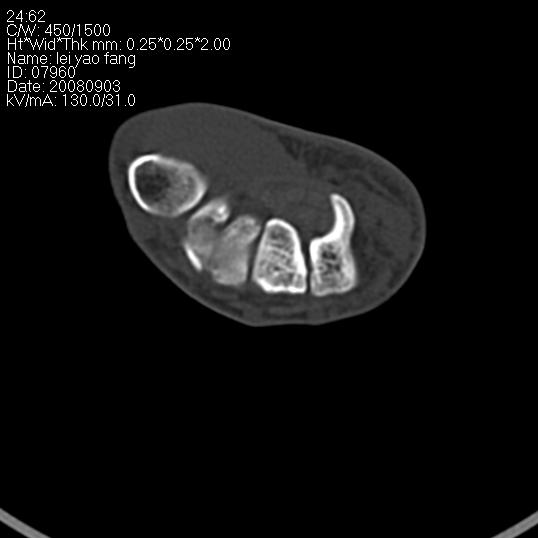

以下是引用杀毒软件在2008-9-4 17:41:00的发言:[br]考虑----舟骨囊肿